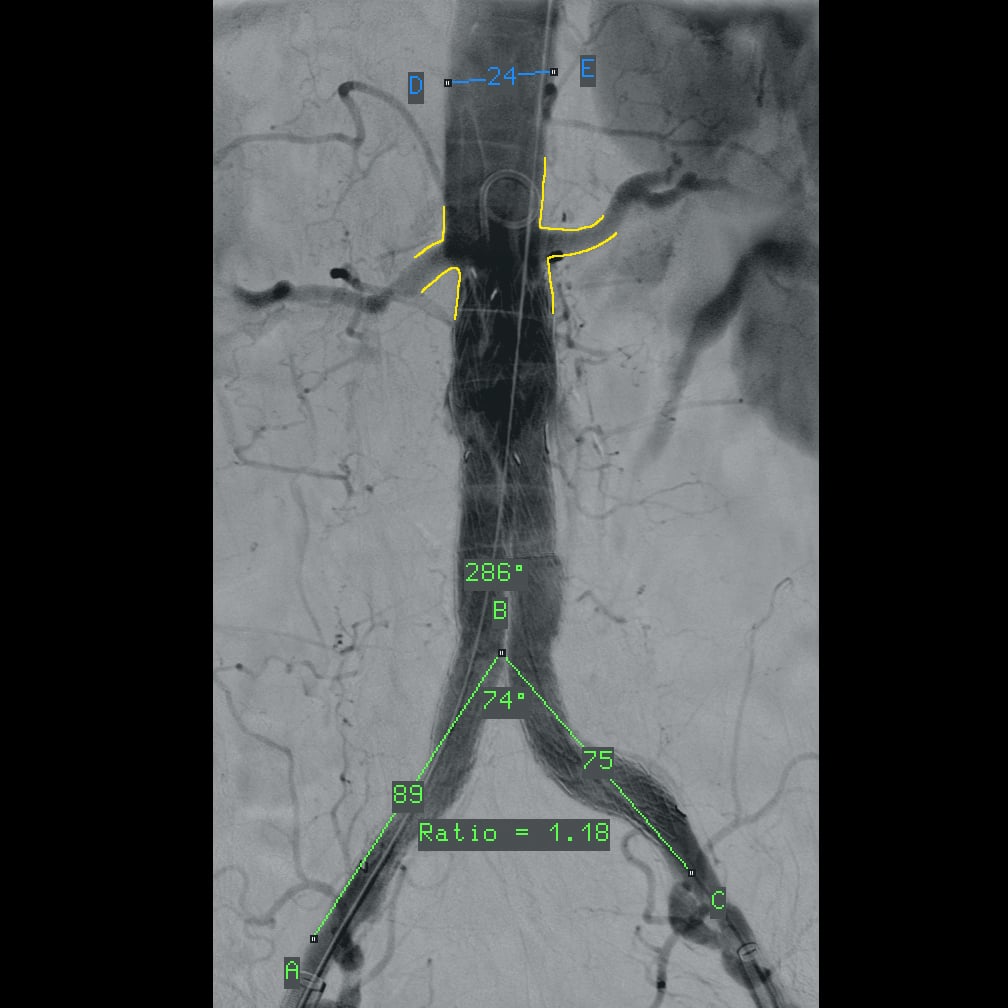

- программный пакет для сосудистой хирургии,

Полное отсутствие искажений снимков в сочетании с высоким динамическим диапазоном широко востребованы как при сложных операциях в нейрохирургии, сосудистой хирургии, инвазивной радиологии, так и в гибридных областях применения, а также в ортопедии, травматологии. В сосудистой хирургии особенно важны высокий динамический диапазон и пространственное разрешение, обеспечивающие детальную визуализацию даже мельчайших сосудов. Специализированное программное обеспечение SmartVascular позволяет проводить настройку системы для васкулярных операций и сосудистой хирургии.

В ходе проведения рентгенохирургических вмешательств хирург имеет возможность на референтном мониторе рабочей станции осуществлять просмотр и обработку только что полученных 3D изображений, выполнять реконструкцию полученных данных для получения объемных изображений различного разрешения и размера поля, проводить измерения в ортогональных проекциях, выбирать оптимальный угол доступа.